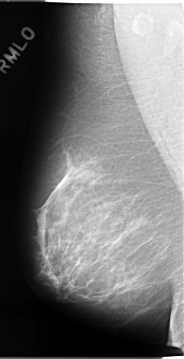

C_0075_1.RIGHT_MLO

ics_version 1.0

filename C-0075-1

DATE_OF_STUDY 10 1 1994

PATIENT_AGE 51

FILM_TYPE REGULAR

DENSITY 2

DATE_DIGITIZED 7 11 1997

DIGITIZER LUMISYS LASER

RIGHT_MLO LINES 4664 PIXELS_PER_LINE 2392 BITS_PER_PIXEL 12 RESOLUTION 50 NON_OVERLAY